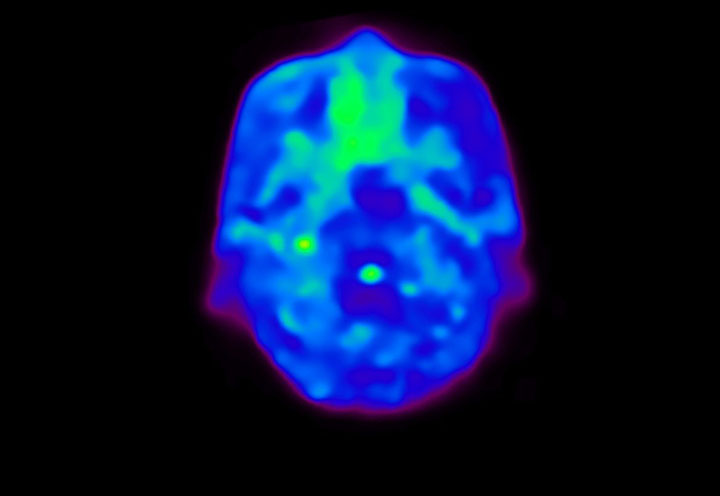

Head / Case4 : Amyloid

Coronal

Courtesy : Kindai University Hospital

- Injected dose: 3.21 MBq/kg, 18F-Flutemetamol

- Uptake time: 100 minutes

- Scan time: 20 minutes